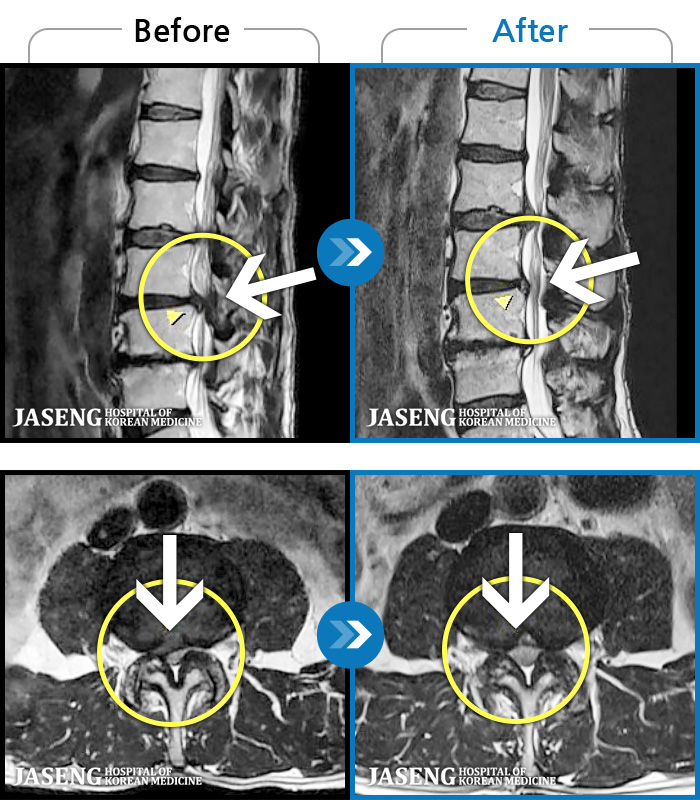

허리에 갑작스럽게 고통스러운 통증으로 내원해서 디스크라는 병명에 놀랐고 무서웠는데 따뜻하고 친절한 진료로 일단 마음이 안정이 되었고 무엇보다 수술없이도 치료가능 할꺼라는 말씀에 위안이 되면서 이선생님만 믿고 치료를 받으면 난 살겠다 라는 마음을 갖게 되며 입원치료를 받기 시작합니다. 침맞는 두려웅, 허리통증으로 유별나게 겁이 많은 나였지만 불편한내색 한번 없이 치료를 해주시고 안정을 주시니 말을 안해도 느껴지는 따뜻한 의료진이 내 주치의인게 너무 감사할따름이였습니다. 하루하루 치료과정에 상태도 꼼꼼히 체크해주시고 정말 거즘 기여서 병원을 들어와서 두발로 씩씩하게 퇴원을 하게 도와주신 장영우원장님 진심으로 감사드리고 자생한방병원에 따뜻한 의료진이 있어 안심이 됩니다

의료진도 치료 방법도 무지한 상태에서 입원한후 통증으로 고생하신 시어머니는 치료방법의 차이로 몇번을 퇴원할까 다른 병원으로 옮길까를 고민하던중 장원장님을 만나 치료후 맘이 바뀌었습니다

자상한 장원장님 울원장님덕에 업혀서 병원들어왔는데 걸어서 퇴원합니다~^^비록 침은 무지하게 아팠으나~ 그침이 내 몸속 신경들을 짖누르고 있는 나쁜것들을 해치우는 정의로운 바늘침!ㅠ한방에~효과짱! 장원장님덕에 침! 을 좋아하게 되었어요~^^ 앞으로 양방보다 한방병원을 더 선호할거 같습니다~^^

살짝만 움직여도 허리가 끔벅거리고 아프고 일어나거나 눕지도 잘 못하고 걸음도 제대로 못걷고 옷도 못입을정도로 통증에 시달렸읍니다. 입원첫날 원장님한테 침맞고 통증이 좀 가라앉았어요 MRI 찍어보니 왼쪽디스크는 터졌고 6번은 터지기 직전 3 4 번은 부어있고 12번 1번은 심각한상태구요 몇일 통증치료하며 끔벅거리는게 없어 살겠더군요 종아리 발바닥 발등이 저려 무척힘들었는데 치료받으며 저린것도 허리아픈것도 많이 좋아졌어요 자금은 걷는것도 훨씬가벼워 졌어요 40대 후반 나이로 내가 벌써 이렇게 몸을 못쓸정도로 아프나 싶어 암담했었는데.. 치료받으며 좋아지니 마음도 훨씬 가볍네요 늘 친절한 모습으로 그날그날 상태를 살펴보며 정성껏 치료해 주시는 원장님 넘~~ 감사합니다!! 우리 원장님??????